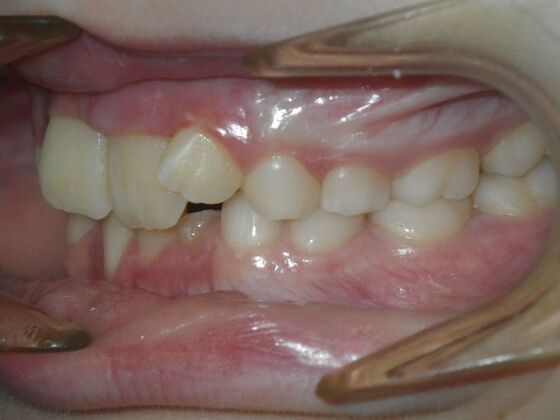

This sweet patient presented with constricted upper and lower arches and blocked out, rotated upper and lower anterior teeth. The upper centrals were leaning backward and had the lower arch captured preventing anterior advancement. Treatment was begun on the upper arch first, followed with placement of lower lip bumper to allow for lateral and anterior development of lower arch. Eventually placed lower brackets with strategic slenderizing of primary teeth to allow permanent incisor to assume their proper placement. All accomplished within 12 months and straight-wire appliances.